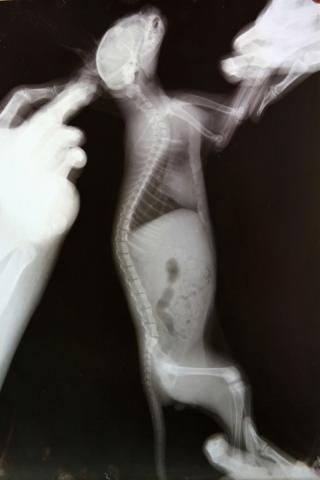

Здравствуйте. У меня приёмный котёнок-подобрашка. Был подобран на улице девушкой волонтёром в первых числах августа, примерно в 2-х месячном возрасте. У котенка расстройства координции. Светлана сделала котёнку рентген, на котором выявлено повреждение 1 шейного позвонка. Первично было назначено: пирацетам, ловетта, фуросемид; далее добавлены мильгамма, преднизолон. Переназначение от другого врача: Мильгама, Нейромедин 0,3*2р/д 15 дней. Курс Нейромедина проведён уже 2-х кратно. Улучшения незначительные, недолговременные. Нарушения координации выражются в треморе головы при малейшем возбуждении (бьётся носом об тарелку, когда кушает), дискоординация движения ног при ходьбе- спина не выпрямляется, задние ноги находят на передние- заваливается на бок, плохо развиты задние конечности, передние контролирует лучше. Планируем в ближайшее время МРТ. Какой отдел нам делать, посоветуйте. Буду рада любой информативной помощи. Спасибо! Это наши снимки.

Извините, как-то пропустила вашу тему. Снимки нечеткие, рассмотреть масштаб трагедии я по ним не могу, тем более снимки сделаны только в сагиттальной проекции, а хотелось бы увидеть и фронтальную.

Tella, Михаил Александрович! Очень благодарна вам за содержательные ответы!!!! Уточню, так как снимки выложены, действительно, не в очень хорошем качестве. Врач, наблюдающий Севу и назначивший нам последнее лечение увидел на снимке трещину на атланте. Где порекомендуете провести нам подобное исследование и возможную операцию? Специализируетесь-ли вы в этом направлении?

Лично я специализируюсь именно на этом направлении. Но про трещину на атланте - как то очень сомнительно. В таком, как у Вас, возрасте кости не ломаются, а, скорее, гнуться. И кости позвонков очень эластичны. Да и трещина если и есть, то что плохого? Трещина - это перелом без смещения. А раз нет смещния то в чем может быть проблема?